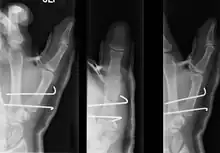

Bennett fracture on x-ray | |

- For Bennett fractures where there is between 1 mm and 3 mm of displacement at the trapeziometacarpal joint, closed reduction and percutaneous pin fixation (CRPP) with Kirschner wires is often sufficient to ensure a satisfactory functional outcome. The wires are not employed to connect the two fracture fragments together, but rather to secure the first or second metacarpal to the trapezium.

- For Bennett fractures where there is more than 3 mm of displacement at the trapeziometacarpal joint, open reduction and internal fixation (ORIF) is typically recommended.